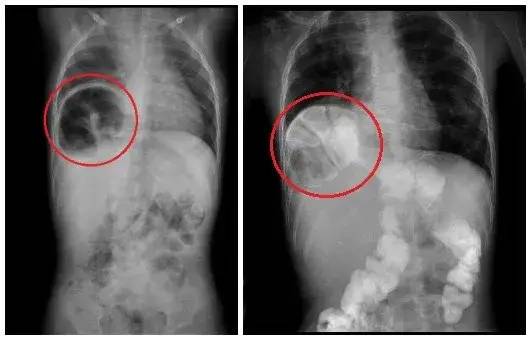

今年刚满1岁的宇宇(化名),自出生以来食量就特别小,刚开始家人以为是挑食。但最近两个月,小宇宇开始频繁呕吐,饭后更是吐得厉害,多地寻医未果。最后经广西柳州市妇幼保健院小儿外科诊断,宇宇得的是一种罕见的疾病——“先天性食管裂孔疝”。也就是说,原本应该待在腹腔的胃,通过横膈肌上的食管裂孔,跑到胸腔里来了。

小宇宇的整个胃和部分肠道,通过食管裂孔已经进入右胸腔内,占据了右侧胸腔的半壁江山。经充分讨论后,医生决定为小宇宇行全腹腔镜下食管裂孔疝矫治手术。

医生在患儿腹壁上打4个5毫米的小洞,将“串门”的胃、结肠等重新拉回到腹腔,切除巨大的疝囊,缝合修补食管裂孔,并进行胃底折叠术,防止胃食管反流。4个小时后,复杂的重建手术顺利完成。术后,宇宇恢复顺利。复查胸腹片提示,胃已降至正常位置。恢复进食后,宇宇没有再出现呕吐,目前已经康复出院。